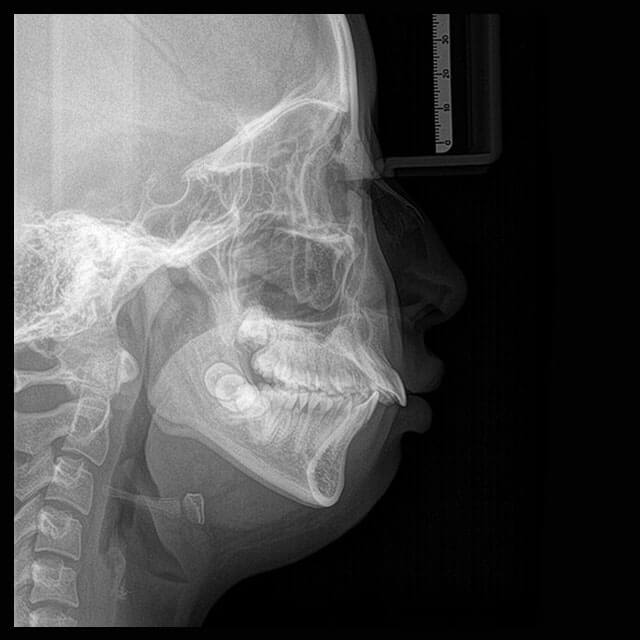

Telerradiografia

A Telerradiografia é um exame radiográfico realizado em posição lateral ou frontal. Através desta imagem são realizadas análises cefalométricas com finalidade ortodôntica ou cirúrgica.